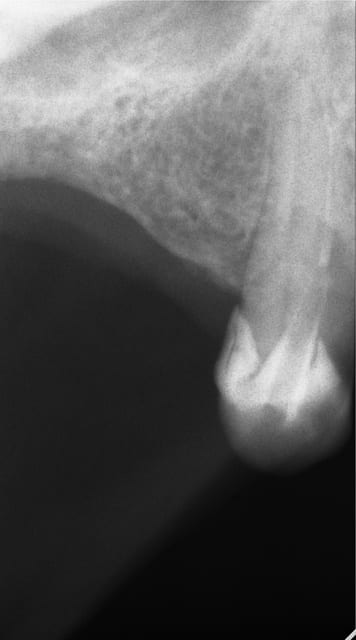

En ce qui concerne la précision, dans ce cas là et pour eviter une augmentation, j ai du placer l implant en mesio palatinal ( voir radio initiale)

En mesurant la hauteur de l os dans le septum ( dans le DVT), celui était seulement de 3 mm. Voilà pourquoi l´implant n est pas dans le septum. L´os a été condensé,la stabilité primaire a donc pu atteindre 50 Ncm.

"la meilleure des augmentations est pas d´augmentation"